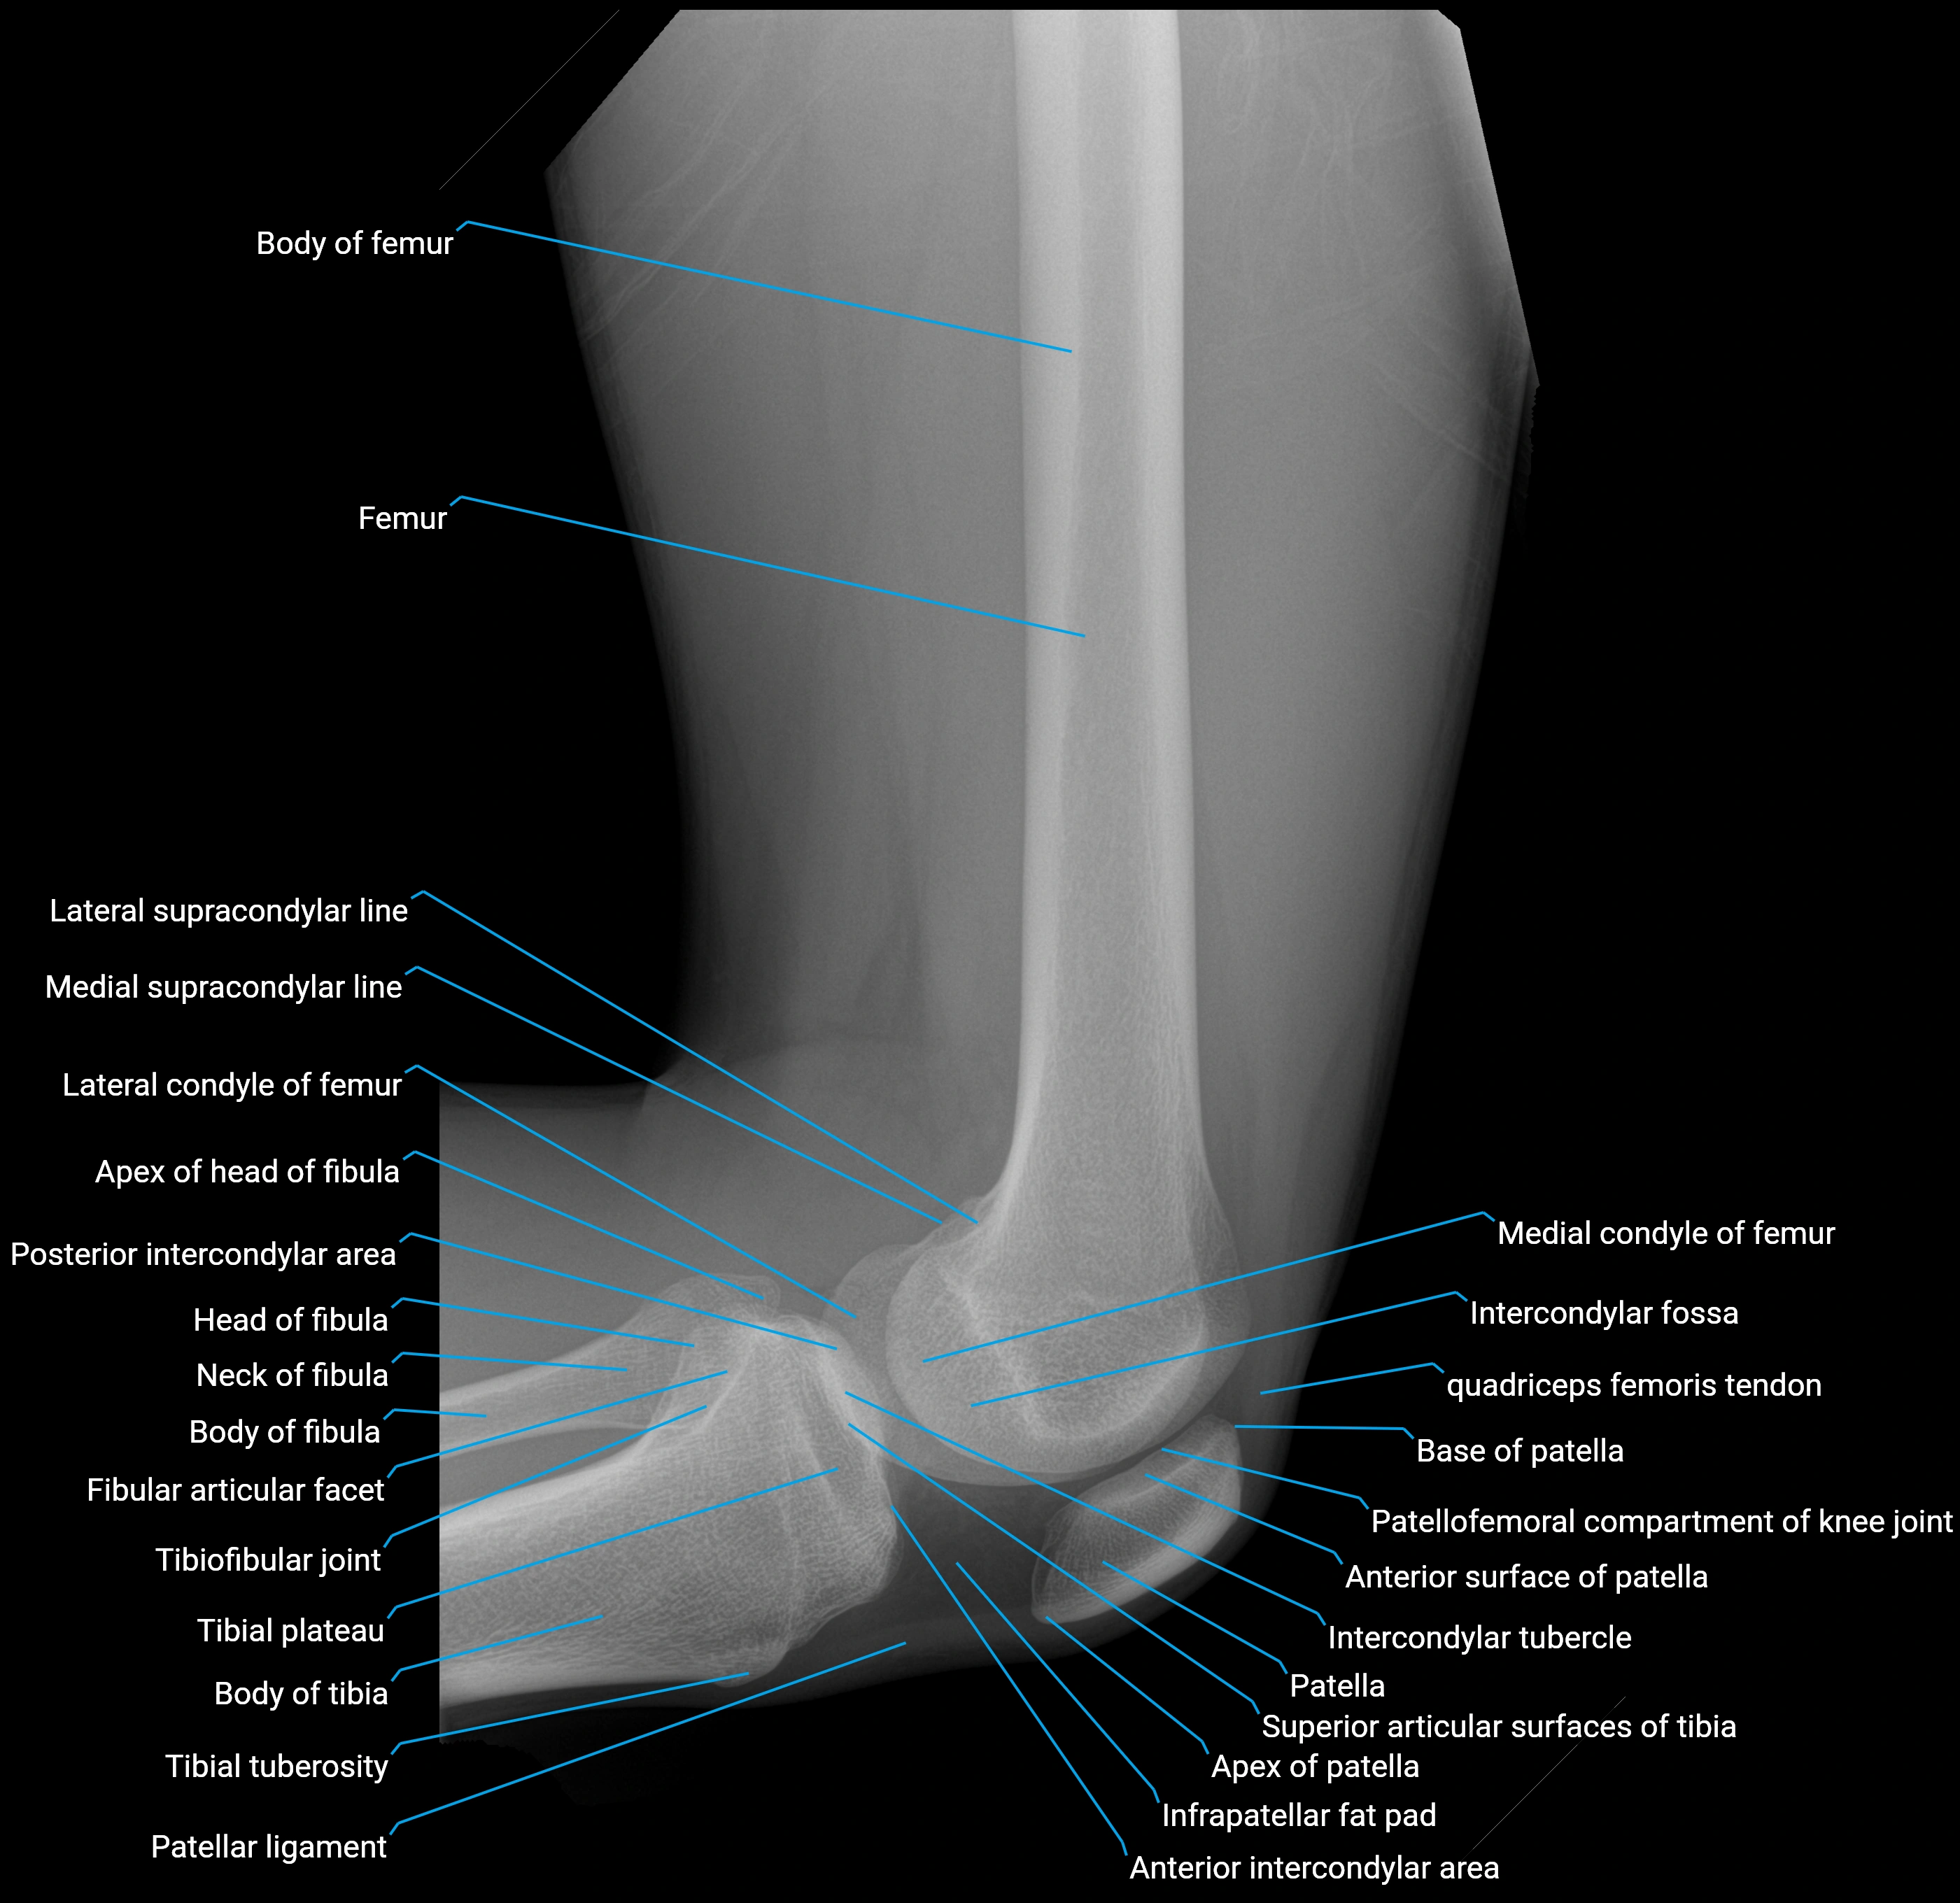

Structure and Relations

• Superior and anterior labrum: thickest portions, stabilizing against anterior dislocation

• Inferior labrum: blends with the transverse acetabular ligament bridging the acetabular notch

• Relations:

• Medial: acetabular articular cartilage

• Lateral: hip joint capsule

• Inferior: transverse acetabular ligament

• Superior: femoral head